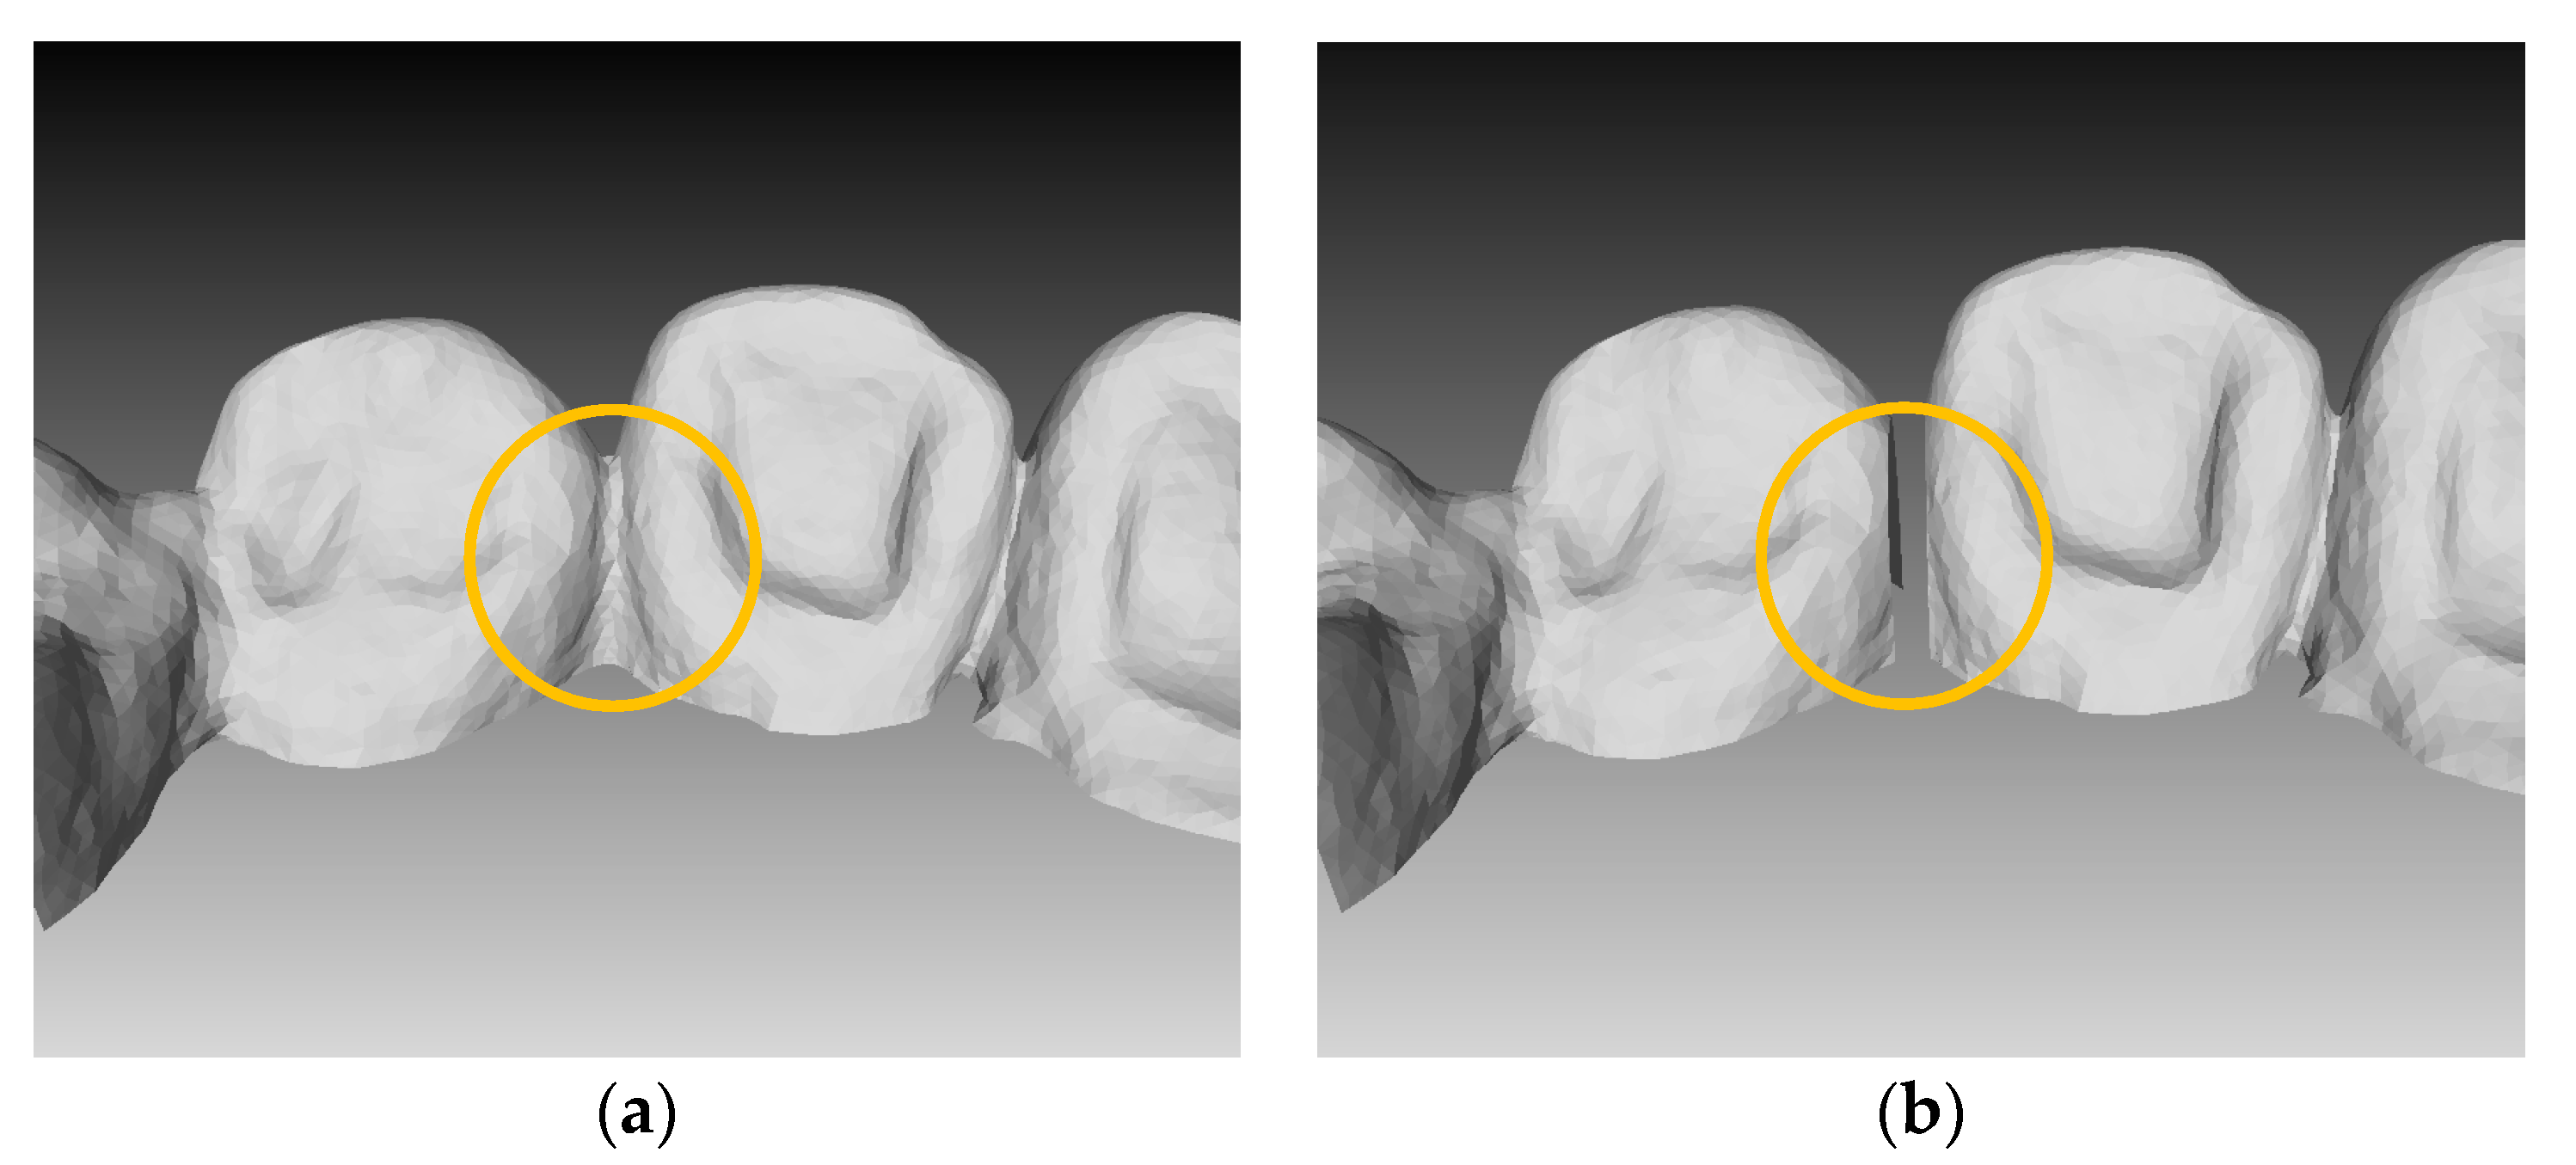

3.1. Result of Image Completion

3.2. Results of Tooth Segmentation

3.2.1. Tooth Model

3.2.2. Accuracy Measurement Process

3.2.3. Measurement Accuracy Results

4. Conclusions